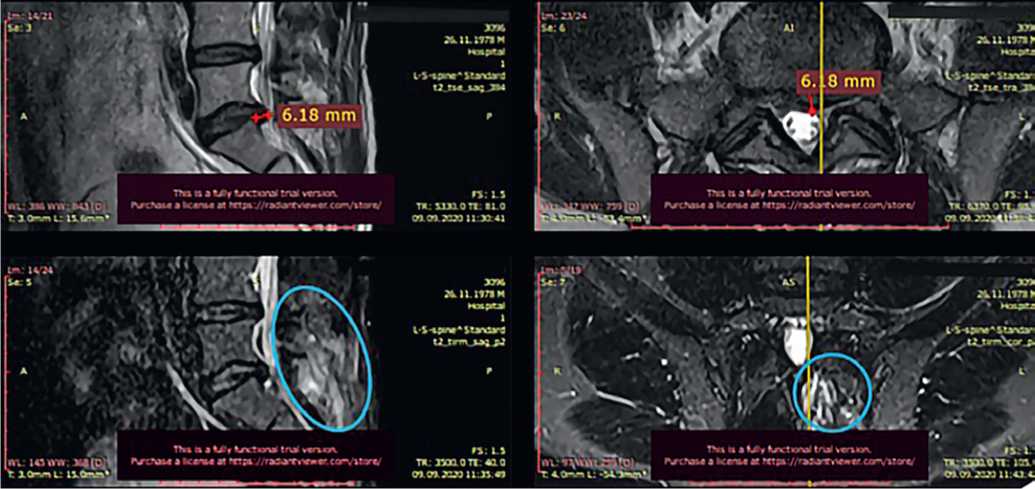

Пациент И., 41 года, обратился в Центр китайской медицины «Синь-я-Чжу» 09.09.2020 с жалобами на постоянную тянущую боль в пояснице с иррадиацией в левую нижнюю конечность. Резкий болевой синдром пациент отмечал даже при легком наклоне вперед, при попытке встать со стула и при ходьбе.

При МРТ от 09.09.2020 обнаружена грыжа диска L5–S1 размером 6,2 мм, отечность окружающих тканей (рис. 6).

Рис. 6. Исходная магнитно-резонансная томограмма пациента И. при обращении 09.09.2020: A) саггитальные срезы, B) аксиальные срезы на уровне межпозвонкового диска L5–S1

Fig. 6. Initial magnetic resonance imaging of patient I. upon presentation on 09.09.2020: A) sagittal sections, B) axial sections at the level of the intervertebral disc L5–S1

После курса акупунктуры болевой синдром купирован. При контрольной МРТ от 28.12.2020 отмечено уменьшение грыжевого выпячивания до 5,3 мм (рис. 7).

Рис. 7. Контрольная магнитно-резонансная томограмма пациента И. после курса акупунктуры 28.12.2020: A) саггитальный срез, B) аксиальный срез на уровне межпозвонкового диска L5-S1

Fig. 7. Control magnetic resonance imaging of patient I. after acupuncture course on 28.12.2020: A) saggital slice, B) axial slice at the level of intervertebral disc L5-S1

В дальнейшем пациент И. «для закрепления успеха» в течение 5 месяцев получал лечебные процедуры у кинезиотерапевта и остеопата, однако эффект получился обратным: вновь появились боли с тенденцией к интенсификации, пациент не мог стоять, сидеть и ходить. Трижды проведены анестезирующие блокады — без эффекта. При МРТ от 06.05.2021 выявлена парамедианная грыжа L5–S1 размером 7,8 мм (рис. 8).

Рис. 8. Магнитно-резонансная томограмма пациента И. при повторном обращении 06.05.2021: A) саггитальный срез, B) аксиальный срез на уровне межпозвонкового диска L5-S1, C) еще один саггитальный срез

Fig. 8. Magnetic resonance imaging of patient I. upon return visit on 05.06.2021: A) sagittal section, B) axial section at the level of the intervertebral disc L5-S1, C) another sagittal section